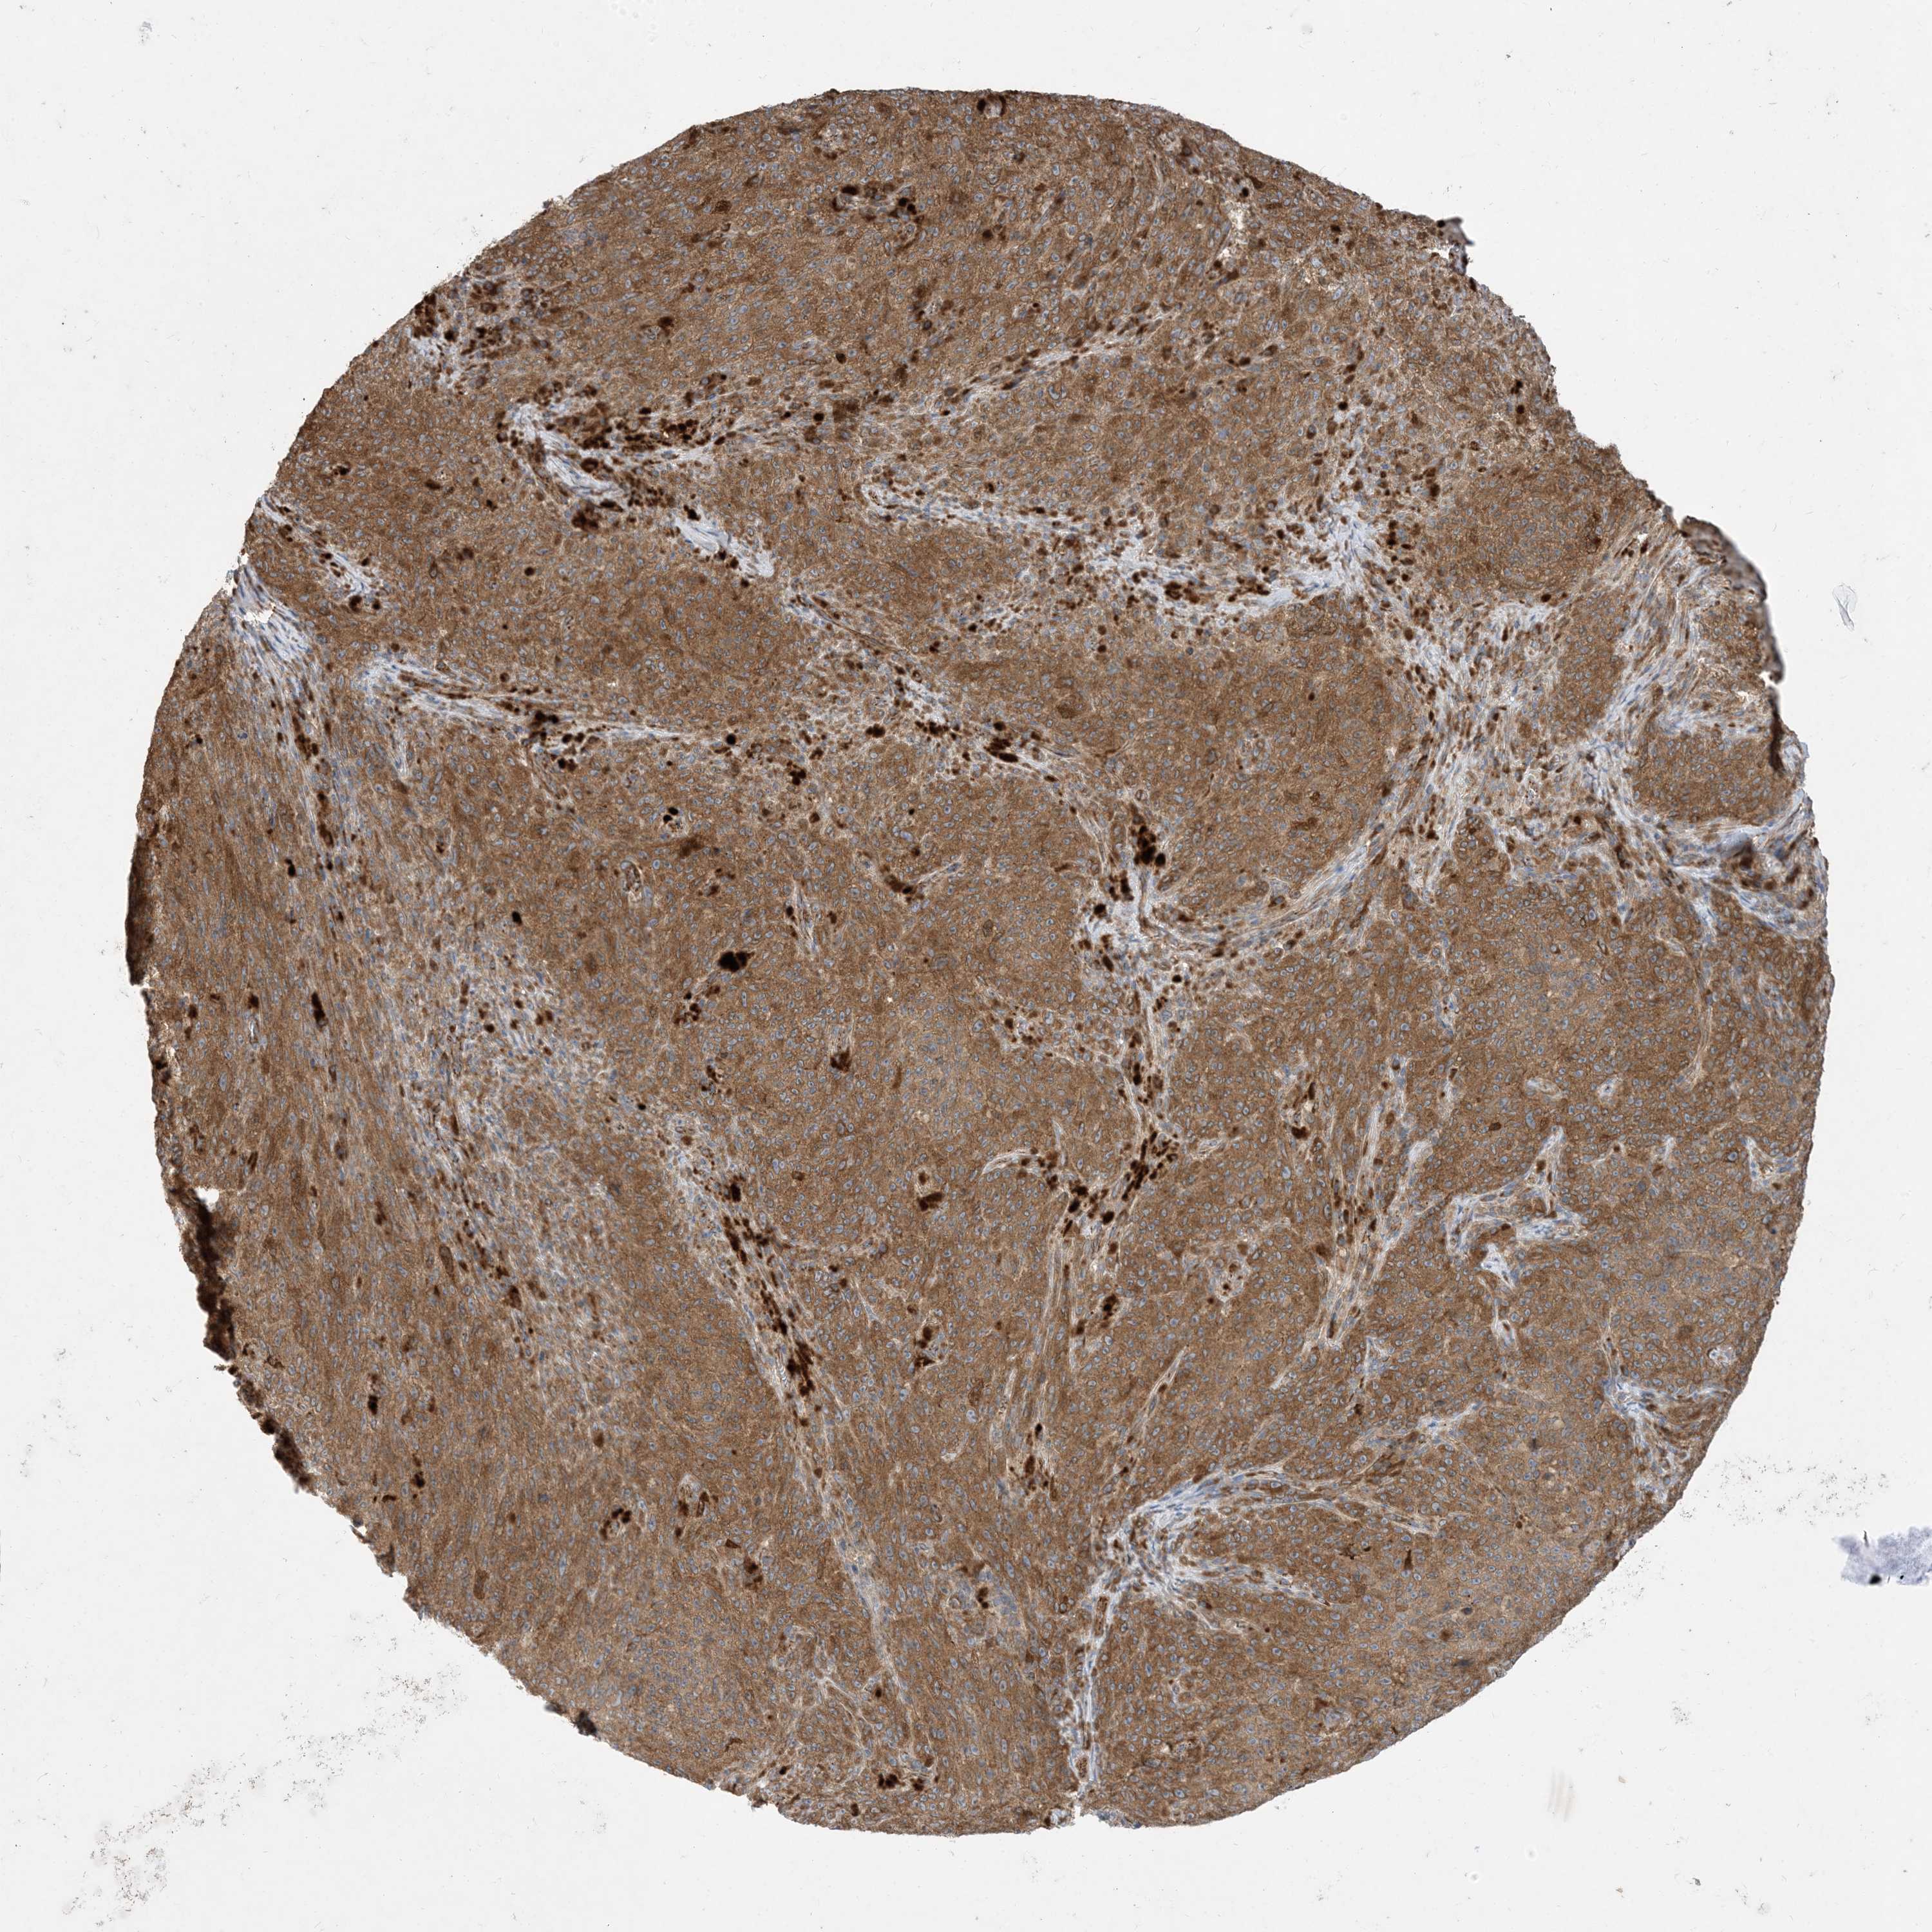

MELANOMA - Protein expressioni

A mouse-over function shows sample information and annotation data. Click on an image to view it in a full screen mode. Samples can be filtered based on level of antibody staining by selecting one or several of the following categories: high, medium, low and not detected. The assay and annotation is described here.

Note that samples used for immunohistochemistry by the Human Protein Atlas do not correspond to samples in the TCGA dataset.

Antibody stainingi

Antibody staining in the annotated cell types in the current human tissue is reported as not detected, low, medium, or high, based on conventional immunohistochemistry profiling in selected tissues. This score is based on the combination of the staining intensity and fraction of stained cells.

Each image is clickable and will lead to virtual microscopy that enables deeper exploration of all samples and also displays staining intensity scores, fraction scores and subcellular localization as well as patient and tissue information for each sample.

Antibody HPA035599

Staining

High

Medium

Low

Not detected

Intensity

Strong

Moderate

Weak

Negative

Quantity

>75%

75%-25%

<25%

None

Location

Nuclear

Cytoplasmic/membranous

Cytoplasmic/membranous,nuclear

Malignant melanoma, NOS

Malignant melanoma, Metastatic site